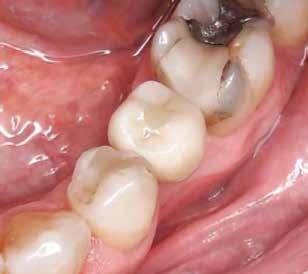

A CT metszetekben a 48-as gyökerei körbeölelik a canalis mandibularist, amelyet piros nyíllal jelöltünk a fotókon.

Szeretnék mutatni néhány ábrát az egyik bonyolult esetről, a közelmúltból. A CT-n látszik, hogy a három gyökér teljesen „körbenőtte” az ideget. Van olyan frontális metszeti kép, ahol csak a gyökerek vannak a nervus körül, ezen a szakaszon egyáltalán nincs meg a csontos fala a canalisnak. Szeparációs technikával, viszonylag könnyen, minimális traumával, szövődménymentesen sikerült eltávolítani a fog minden részét. A várakozásnak megfelelően, a beteg nem számolt be paraesthesiáról.